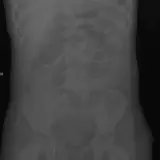

Casos totalmente interactivos con las herramientas que esperaría de un PACS: scroll, ventana, zoom, pan, mediciones, ROI y modo de pantalla completa.

Desplace, arrastre, ajuste ventana y amplíe como en una estación PACS de trabajo